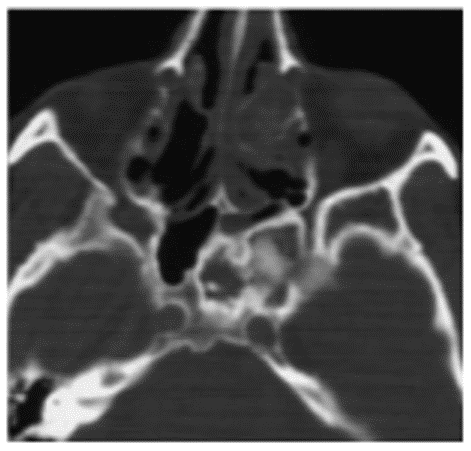

Фиброзная дисплазия на КТ характеризуется наличием относительно однородной, напоминающей матовое стекло, ткани плотностью, примерно, от 300 до 450 ед. Н, что ниже обычных денситометрических значений для спонгиозного слоя кости и соответствует плотности фиброзной ткани (рисунок 5).

Рис. 5. КТ околоносовых пазух, аксиальная плоскость. Фиброзная дисплазия верхнечелюстной (А), лобной (Б) пазух